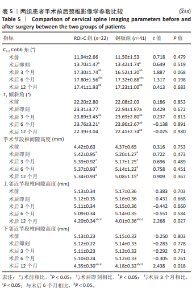

2.6 手术前后影像学评估 两组患者术后C2-7 Cobb角、T1倾斜角,椎间隙高度均较术前显著改善,两组组内不同时间点的C2-7 Cobb角、T1倾斜角,椎间隙高度比较存在显著差异(P < 0.001),而不同分组之间的评分差异无显著性意义(P > 0.05),并且两组在不同时间点的趋势也无显著差异(P > 0.05)。 ROI-C组术后即刻、术后3,6,12个月的C2-7 Cobb角、手术节段椎间隙高度及术后3,6个月的T1倾斜角较术前均显著增加;术后3,6,12个月的C2-7 Cobb角、术后3个月的T1倾斜角均较术后即刻明显增加;术后6个月的C2-7 Cobb角较术后3个月明显增加,差异有显著性意义(P < 0.05)。钢板组术后即刻、术后3,6,12个月的C2-7 Cobb角、手术节段椎间隙高度及术后即刻、术后3,6个月的T1倾斜角均较术前明显增加;与术后即刻相比,钢板组术后3,6,12个月的C2-7 Cobb角及术后3,6个月的T1倾斜角均明显增加;术后6个月的C2-7 Cobb角较术后3个月明显增加,术后12个月的T1倾斜角较术后3个月明显减小;术后12个月的T1倾斜角较术后6个月明显减小,差异有显著性意义(P < 0.05)。见表5。"